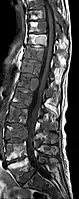

- Comparaison scanner/IRM pour des métastases ostéolytique d'un cancer du sein dans la colonne vertébrale

Scanner sagittal reconstruit, représentation dans la fenêtre osseuse. Comme la patiente avait des métastases dans toutes les régions du corps, elle ne pouvait pas lever les bras pour l'examen, ce pourquoi les mains sont présentées.

Scanner sagittale, parties molles. Outre les métastases dans la colonne vertébrale, qui envahissent en partie le canal médullaire vers l'arrière, métastases aussi dans le sternum. Plus des métastases dans le foie.

IRM natif avec pondération T1.

IRM sagittal natif avec pondération T1. On voit clairement l’extension jusqu'aux lames vertébrales.